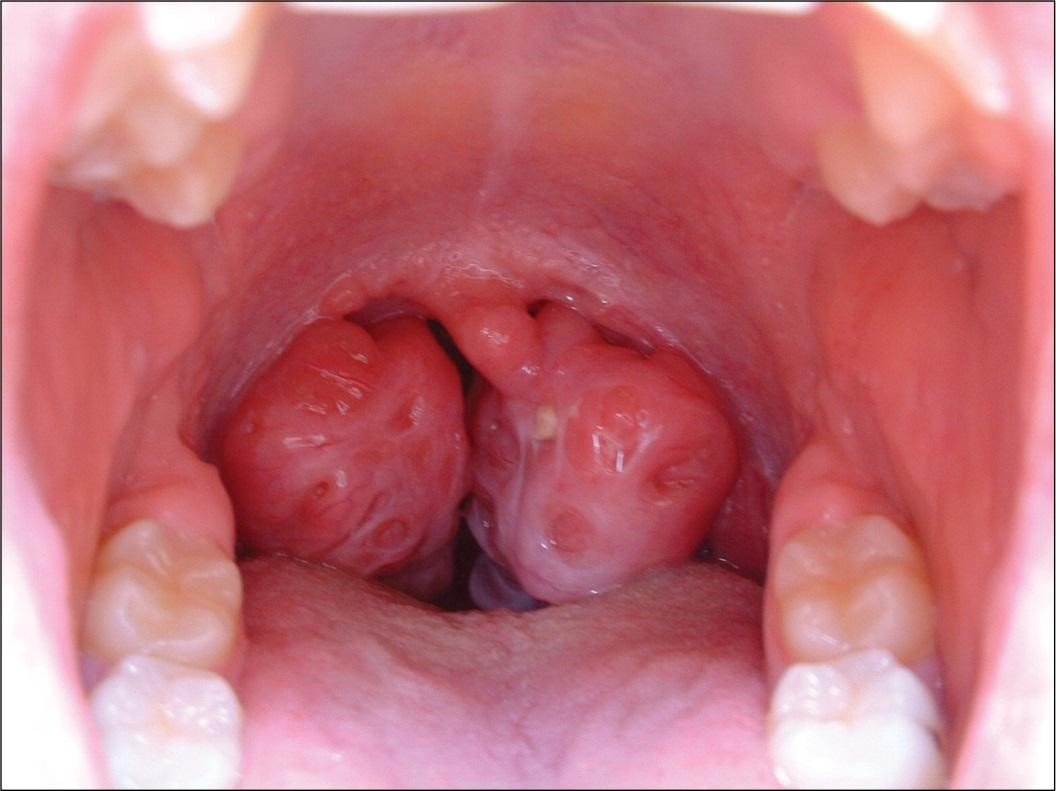

– Ho, đau rát cổ họng, amidan sưng to, đỏ, bề mặt xuất hiện những mủ trắng li ti.

Những dấu hiệu thấy rõ ở amidan bị viêm.